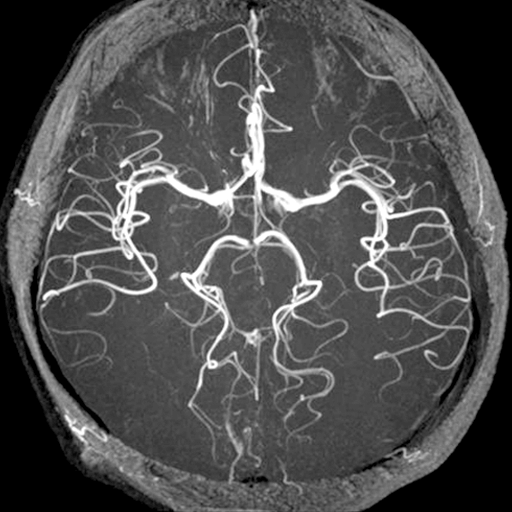

MRAとは、磁気の力を利用して血管の状態調べる検査です。頭部のMRAでは、脳の血管だけに特化して病変の有無を確認します。くも膜下出血の原因となる脳動脈瘤のスクリーニング検査として有用であり、脳血管の閉塞や狭窄、未破裂椎骨動脈解離、脳血管奇形などを検出します。MRAは磁場による血流の信号を画像化しています。磁場が弱く画像の不鮮明な場合、擬態的に病巣(動脈瘤、狭窄等)に見えてしまうようなことが生じることがあります。しかし、磁場強度を3.0テスラに上昇させると高分解能を有する画像が得られ、細かいところがよく見えるようになり、病変の診断能力が著明に向上します。(そのため当院では頭部検査に3.0テスラMRIを推奨しています。)

頭部領域の検査は、脳血管の診断能が顕著に向上している3.0テスラMRIにて検査を行います。